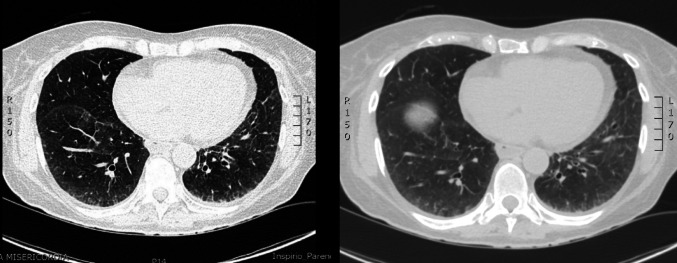

系统性硬化症(SSc)和淀粉样变是罕见的复杂疾病,损害多个器官的功能,每种疾病都有不同的致病机制:SSc的自身免疫和淀粉样变的错误折叠蛋白沉积。我们报告了第一例57岁女性并发SSc和系统性AL淀粉样变并多器官受累的病例,其中淀粉样变治疗导致SSc症状显著改善。患者于2023年夏季出现疲劳、用力性呼吸困难、上腹部疼痛和晕厥发作。调查显示左心室厚度轻度增加,NT-proBNP和肌钙蛋白升高,冠状动脉造影阴性。随后,她被诊断为SSc,多器官受累,活检证实为系统性AL淀粉样变。采用改良的Dara-CyBorD方案治疗可改善SSc症状,特别是在呼吸困难和皮肤受累方面。这是首次报道的SSc与系统性AL淀粉样变并存的病例。该患者对淀粉样变治疗反应良好,提示潜在的重叠治疗益处。多学科的方法是必不可少的,需要进一步的研究来探索这两种罕见疾病之间的治疗相互作用。

Systemic sclerosis (SSc) and amyloidosis are rare, complex conditions that impair the function of multiple organs, each with distinct pathogenic mechanisms: autoimmunity for SSc and misfolded protein deposition for amyloidosis. We present the first documented case of a 57-year-old woman with coexisting SSc and systemic AL amyloidosis with multi-organ involvement, in which treatment for amyloidosis led to a notable improvement in SSc symptoms. The patient presented experiencing fatigue, exertional dyspnea, epigastric pain and syncopal episodes in the summer of 2023. Investigations revealed mild increase in left ventricle thickness, elevated NT-proBNP and troponin with negative coronary angiography. She was subsequently diagnosed with SSc with multi-organ involvement and systemic AL amyloidosis confirmed by biopsy. Treatment with a modified Dara-CyBorD protocol led to improvement in SSc symptoms, especially in terms of dyspnea and skin involvement. This is the first reported case of SSc coexisting with systemic AL amyloidosis. The patient responded well to therapy for amyloidosis, suggesting potential overlapping treatment benefits. A multidisciplinary approach was essential, and further studies are needed to explore therapeutic interactions between these two rare diseases.